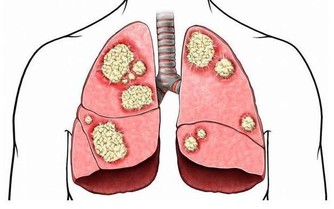

男性45歲後免疫力下降,患病風險高,尤其是前列腺炎、前列腺增生、糖尿病和心血管疾病等,因此一年體檢一次,根據情況來著重檢查某部位,必要時需做防癌篩查。

吸煙、喝酒的男性比比皆是,對身體的影響不容忽視,香煙和酒可連累全身每一個器官,包括心臟、肺部和肝臟、胃部等,所以戒菸戒酒很有必要。